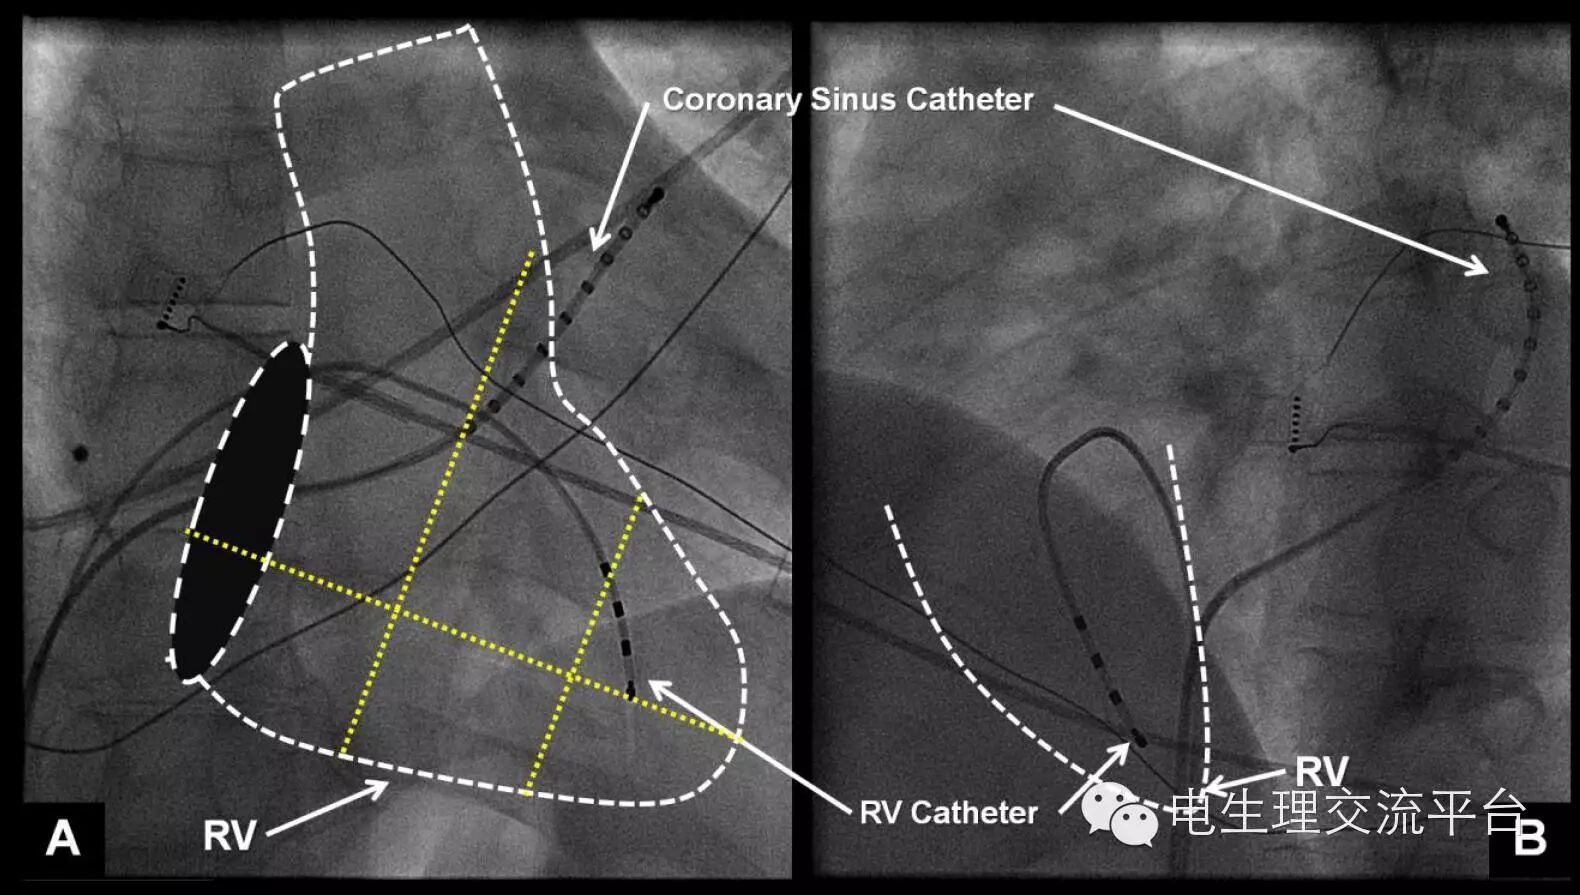

1. (A)、左 (B)前斜位展示了右室和冠状窦电极位置。点线代表右室轮廓,椭圆形黑盘代表三尖瓣环。右室电极远端必须标准化放置在右室心尖部。